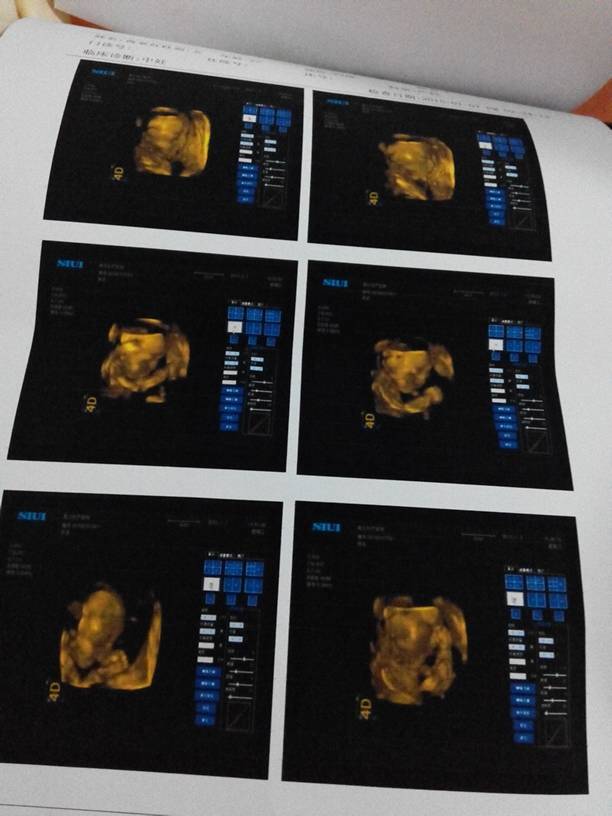

调皮捣蛋小宝宝… 调皮捣蛋小宝宝…… 点击展开 188*****593 2015-01-07 18:24 为您推荐: 其他回答 祝宝妈好运 琳子💄 2015-01-07 21:48 呵呵,,, 溜溜达达转转转 2015-01-07 20:17 宝妈好孕! 小陈妈妈 2015-01-07 19:15 好可爱啊!祝你好运,宝妈妈 189*****389_5tde 2015-01-07 18:50 祝宝妈好孕 緈輻の必勉 2015-01-07 18:48 加载更多 相关问题 调皮捣蛋的小宝宝!妈妈爱你 给小宝宝养乌龟好不好呢? 二岁半小宝宝吃石鸡好不好七月份